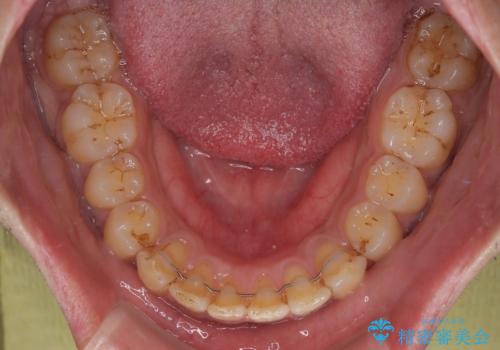

- 上の前歯の正中離開(すきっ歯)と、下顎前歯部の叢生(デコボコ)を主訴に来院された患者様の症例です。

「目立ちにくい装置で治療したい」とのご希望があり、透明のマウスピース矯正であるインビザラインを用いて矯正治療を行いました。

インビザラインは装置が透明で、周囲に気づかれにくいことが大きなメリットです。

取り外しもできるため衛生面でも安心して治療を進めていただけました。